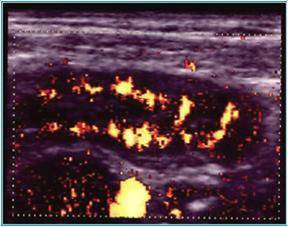

Compresia gradata sonografica este sugestiva pentru stabilirea cu acuratete a diagnsticului de apendicita. Apendicele apare ca o terminatie oarba, un fragment intestinal neperistaltic, cu originea la nivelul cecului. Printr-o compresiune maximala, se masoara diametrul antero-posterior al apendicelui. Testul este considerat pozitiv daca diametrul antero - posterior al apendicelui necomprimat este de 6 mm sau mai mult. Prezenta unui apendicolit stabileste diagnosticul. Imaginea ecografica a unui apendice normal, care este o structura tubulalara inchisa la un capat, usor compresibila, cu un diametru de 5 mm sau mai putin, exclude diagnosticul de apendicita acuta. Studiul este considerat negativ daca apendicele nu se vizualizeaza si nu exista o masa tumorala sau fluid pericecal. Cand se exclude ecografic diagnosticul de apendicita acuta, o scurta evaluare a restului cavitatii abdominale ar fi de preferat pentru stabilirea unui alt diagnostic. La femeile active sexual, organele pelvine genitale ar trebui vizualizate atat transabdominal, cat si transvaginal, pentru a exclude o patologie ginecologica care ar putea cauza durerea abdominala acuta.

Diagnosticul ecografic al apendicitei acute are o sensibilitate de 78 - 96 % si o specificitate de 85 - 98 %. Ecografia poate fi realizata in scop diagnostic la copii si femeile insarcinate, desi aplicabilitatea ei este oarecum limitata in ultimele luni de sarcina.

Fig. 11 Apendicita acuta cu hiperemie parietala